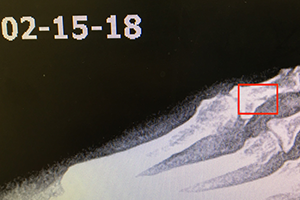

She continued on a regimen of 5 Fastt patches total, and 2 full bottles of Martial to cover 4 weeks on the protocol. During this time the foot was placed in a boot, with use of a scooter, occasional pressure, and walking on the foot for 2 weeks. After the 2nd week she started to walk more, continuing to keep her foot in the boot as needed. By January 15th, 2018 the patient stated she was not walking with the boot anymore, and had started to wean off it the week prior.

The practitioner noted that most of the healing happened in the first 4 weeks, and that more recent x-rays are showing slower change during the remodeling phase of bone growth. The patient was happy with the speedy recovery and back to driving, walking and enjoying life. As an additional note she states that her bone spur has softened and is no longer painful for walking since starting the therapy for her fracture on the same foot.